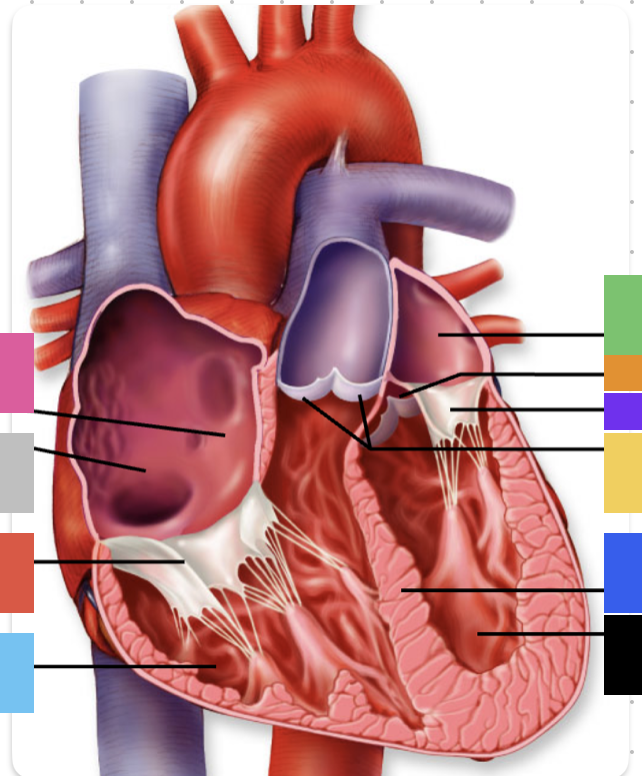

light purple

base

purple

apex

grey

right atrium

pink

right auricle

green

left atrium

green

left auricle

blue

right ventricle

orange

left ventricle

green

coronary (atrioventricular) sulcus

pink

interatrial septum

dark blue

interventricular septum

green

anterior interventricular sulcus

green

posterior interventricular sulcus

orange

aortic valve

yellow

pulmonary valve

red

tricuspid valve (right AV)

purple

bicuspid valve (left AV)

yellow

chordae tendineae

orange

papillary m.

blue

trabeculae carneae - only in ventricles

red

pectinate m. - only in R atrium

pink

fossa ovalis

grey

opening of coronary sinus

green

ligamentum arteriosum

green

fibrous pericardium

blue

parietal pericardium

pink

visceral pericardium (connective tissue) / epicardium (muscle)

purple

myocardium

grey

endocardium

pink

superior vena cava

black arrow

inferior vena cava

black

pulmonary trunk

purple

left pulmonary artery

black

left pulmonary veins

blue

(branches of) right pulmonary artery

yellow

right pulmonary veins

orange

ascending aorta

purple

aortic arch